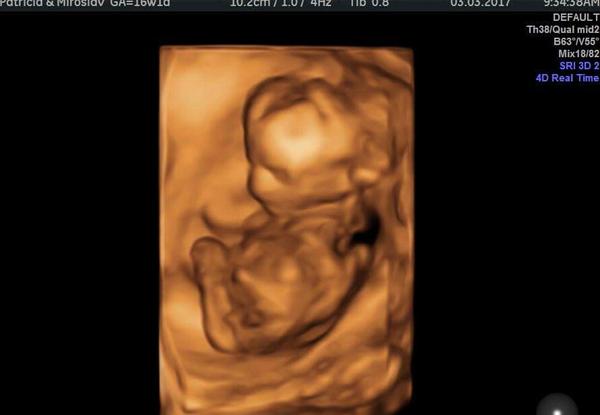

@ikonica Áno tešíme sa veľmi, sme tomu neverili 😄

Ale ja som to tušila, že nosím pod ❤ malú princeznú 🙂